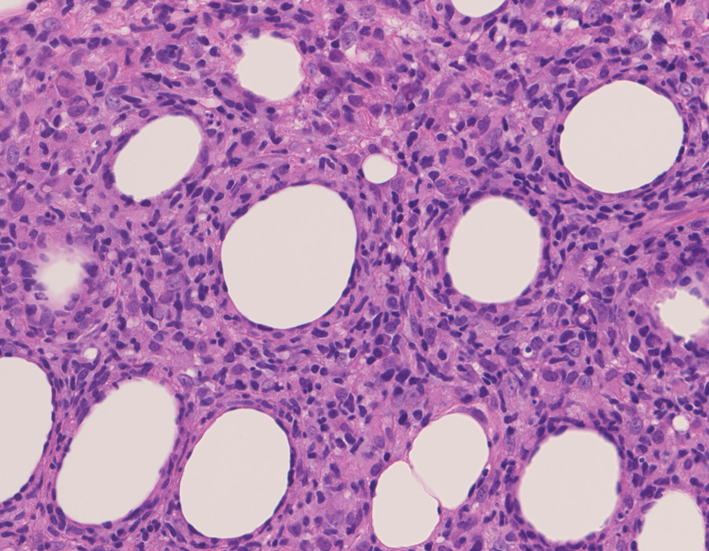

リンパ腫の定義: SPTCLは成熟細胞障害性T細胞(cytotoxic T-cell)由来で、皮下組織に脂肪識炎に似た組織像を呈しながら増殖する悪性リンパ腫。

皮下組織に優位な, 小~中型 Tリンパ球の密な浸潤が特徴。ときに大型リンパ球や組織球が混在する。 リンパ球の異型は, わずかなものから明瞭な異型を示す症例までさまざまである。